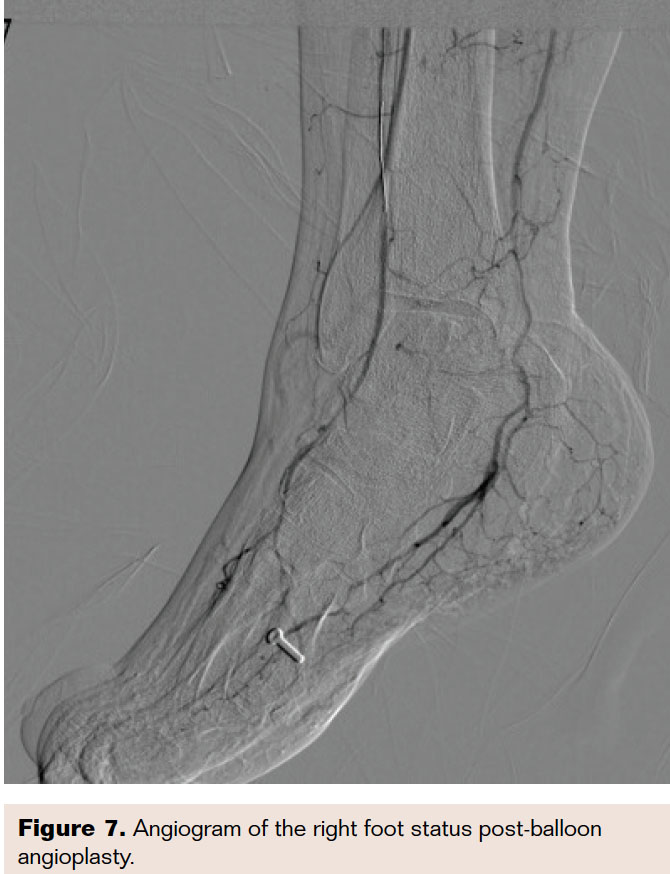

In a retrograde fashion, a 0.014-inch Runthrough wire was advanced in combination with a micro 14 support catheter, which was advanced to the proximal cap of the ATA occlusion and used as a reference (Figure 4). Under guidance of the retrograde wire, the antegrade wire was advanced in the appropriate direction, leading to intraluminal crossing (Figure 5), as confirmed by intravascular ultrasound (IVUS). Balloon angioplasty was then performed using a 2.0 × 150 mm NanoCross balloon with single inflation at 10 atm, followed by laser atherectomy and subsequent low-pressure inflation of the proximal ATA using the same balloon. Final angiograms revealed excellent antegrade flow through the tibioperoneal trunk, ATA, and PTA with 2.5 run-off to the foot (Figures 6 and 7).